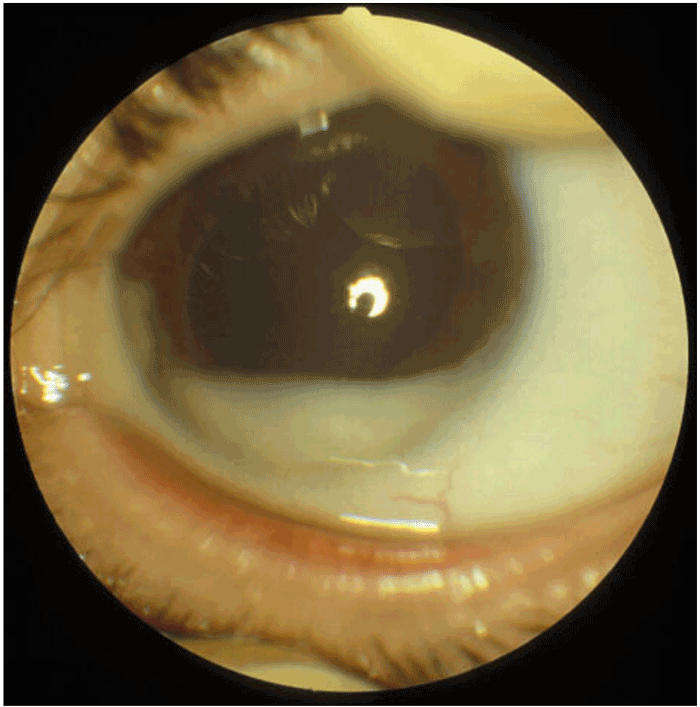

- toute autre cause de leucocorie, comme par exemple une cataracte congénitale (Figure 23) ou un foyer infectieux rétinien (toxocarose, toxoplasmose, etc.).

Figure 23 Cataracte congénitale, responsable d'une leucocorie de l'enfant.